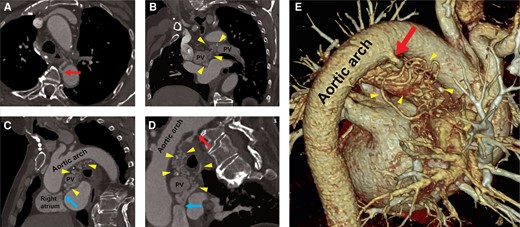

Vores dygtige kollegaer fra Radiologisk afdeling på Aalborg Universitetshospital Louise Tram og Robert Johannes Leusink, har netop publiceret en spændende case-rapport i European Heart Journal med titlen “Mediastinal mayhem: the challenges of incidental thoracic arteriovenous malformations — a case report”.